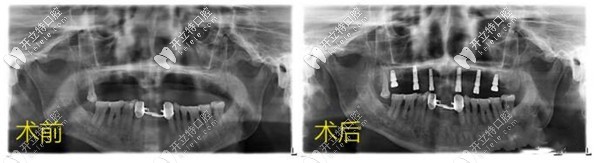

昆明美奧口腔allon4半口種植牙案例分享:牙周病殘根也能修復

昆明牙科美奧口腔半口種植牙發(fā)布時間: 2025-07-01

70多歲老人因嚴峻牙周炎、多顆牙缺失,來昆明美奧口腔找全慶波種植醫(yī)生做allon4下半口種植牙手術修復,術后反饋比之前戴活動義齒假牙要好用的多,而且比較舒適。